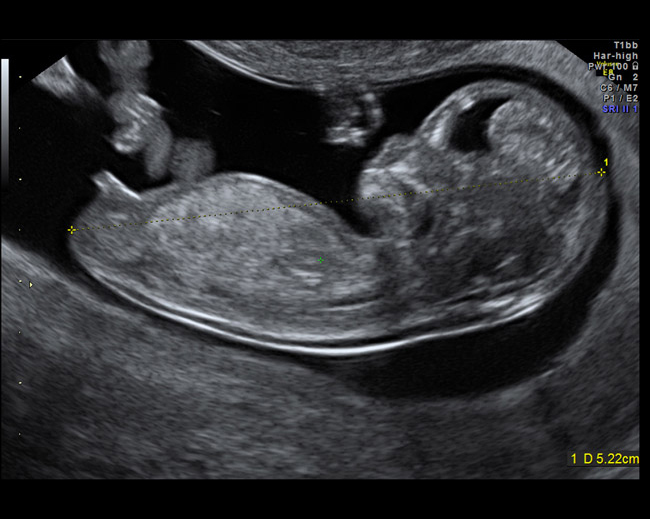

- Ultrason: 14. haftadan itibaren bebeğin cinsiyeti ultrason ile görülebilir. Ancak, kesin sonuçlar genellikle 16. haftadan sonra, özellikle 18-21. haftalarda alınır.

- Bebeğin cinsiyeti ne zaman belli olur? Hamileliğin 16-21. haftaları arasında yapılan ultrason muayenesi ile bebeğin cinsiyeti belirlenebilir. Ancak nadir de olsa yanılmalar yaşanabilir.

- Erkek bebek kaçıncı haftada belli olur? Erkek bebeklerin cinsiyeti genellikle 16-21. haftalarda net olarak belirlenebilir. Ancak bebeğin anne karnındaki pozisyonu bazen net görüntü almayı engelleyebilir.